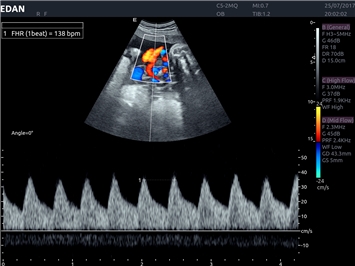

EDAN Acclarix LX4 представляет собой инновационную ультразвуковую систему, построенную на усовершенствованной платформе Acclarix. Сочетание высокого качества визуализации с интеллектуальным рабочим процессом делает эту систему оптимальным выбором для клиник, ценящих эффективность и экономичность.

• Тканевая допплеровская визуализация (TDI)

• Кардиологических исследований

Цветовой допплер:

Постоянно-волновой допплер:

Импульсно-волновой допплер:

Триплексное сканирование:

Дуплексное сканирование: